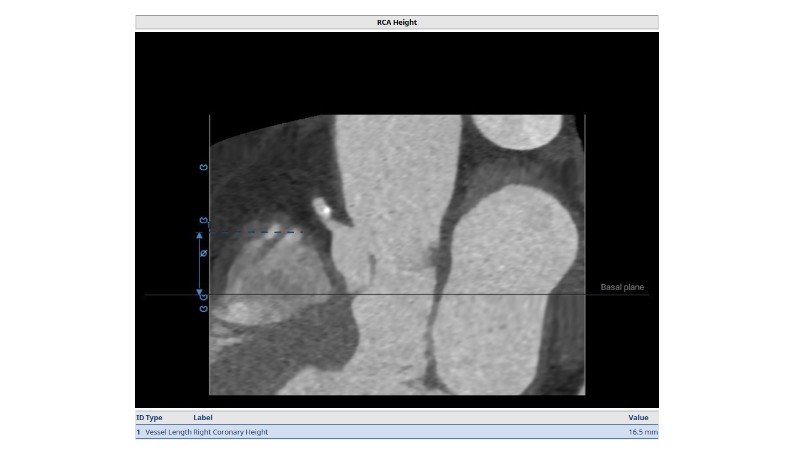

Discover how thoughtful index valve selection and implantation techniques can shape the long-term management of patients undergoing TAVI. This PCR London Valves 2025 session highlights treatment considerations for low- and intermediate-risk patients, explores how valve choice affects the feasibility of future interventions, and examines strategies to achieve optimal and durable clinical outcomes. Follow real patient case with imaging analysis, hemodynamic insights in small annuli, and discussions on planning for future revalving and coronary access.